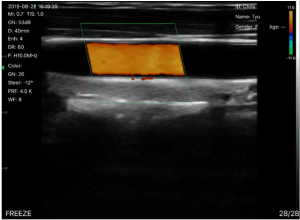

B, B/M, Color doppler version with B+Color, B+PDI, B+PW

Convex Probe frequency:

Convex Probe scan depth:Convex Probe head radius/width:Convex Probe scan angle: |

3.5MHz/5MHz 90/160/220/305mm 45mm 50° |

Linear Probe frequency: Linear Probe scan depth: Linear Probe head radius/width: |

7.5MHz/10MHz 20/40/60/100mm 40mm |

BGain, TGC, DYN, Focus, Depth, Harmonic, Denoise, Color Gain, Steer, PRF